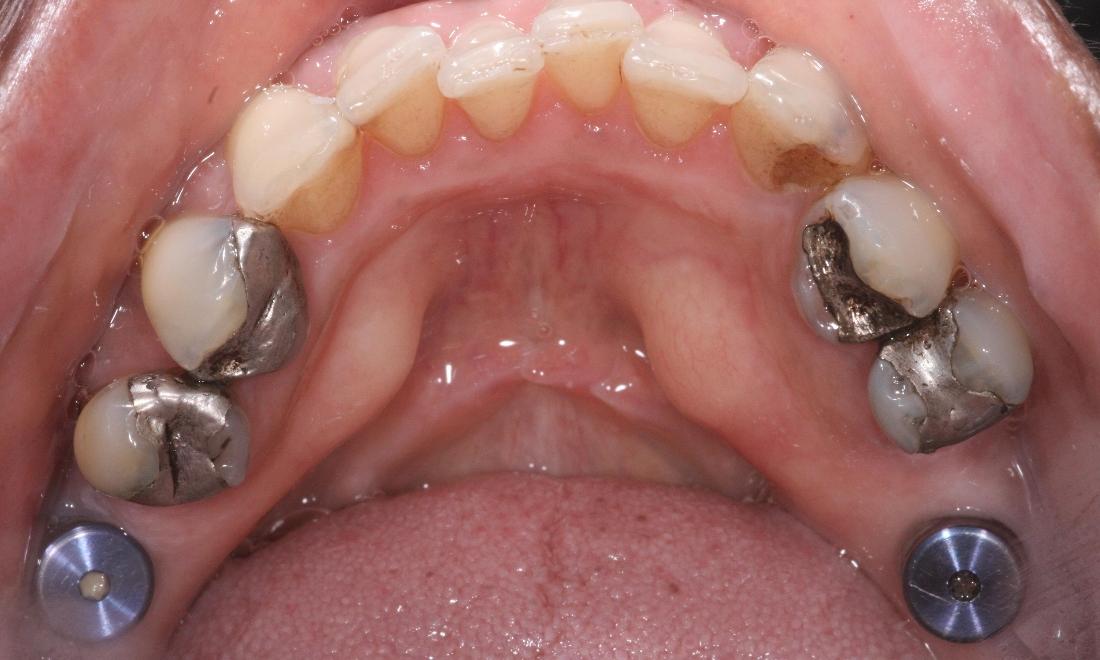

Above all, we are committed to offering and delivering exceptional, comprehensive dental care to each and every one of our clients. Through a unique mix of ultra-contemporary office design elements; the finest dental technologies, materials, and treatments; and a strong emphasis on exemplary customer service, it is our mission to create a practice environment which fosters the highest level of patient comfort safety, and overall satisfaction. We strive to protect the health of our patients and add beauty to their smiles. We will not be satisfied until we have perfected THE ultimate experience - one that includes Five Star service, extraordinary dentistry and makes a positive, lasting impression on the lives of our patients.